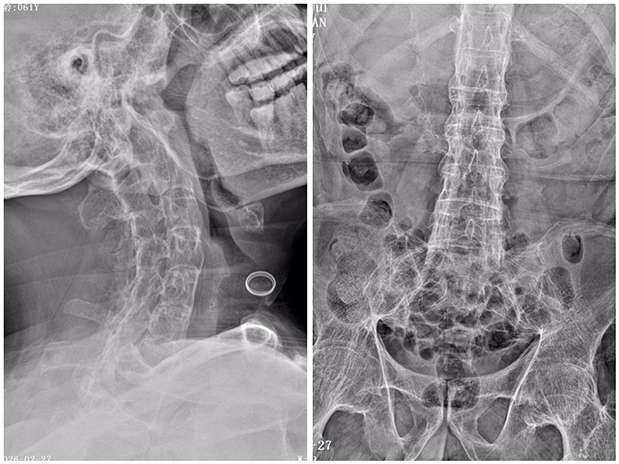

丁某是六安市裕安区苏埠镇人,30年前确诊强直性脊柱炎。这种被称为“不死的癌症”的疾病,如同无形枷锁,慢慢侵蚀着他的脊柱与关节,原本灵活的椎骨关节逐渐被钙化物“焊死”,最终脊柱畸形成“折叠人”状态,无法平卧、抬头困难,连基本生活都难以自理,劳作更是无从谈起。

颈、胸、腰椎及髋关节均已融合,膝关节无活动度。

丁某的状况让医护团队陷入两难。最核心的难题在于“困难气道”与无法平卧的身体状态:强直性脊柱炎导致其颈椎几乎完全融合,寰枕关节活动度严重受限,张口都极为困难,常规气管插管几乎无法完成,一旦麻醉时气道建立失败,患者随时可能因窒息危及生命。同时,长期卧床、骨折创伤与手术应激叠加,使其静脉血栓栓塞症风险评分高达10分,属于高危人群,围术期血栓预防成为另一大难关。更尴尬的是,髋膝关节完全无法活动,连常规手术消毒铺巾都难以开展。